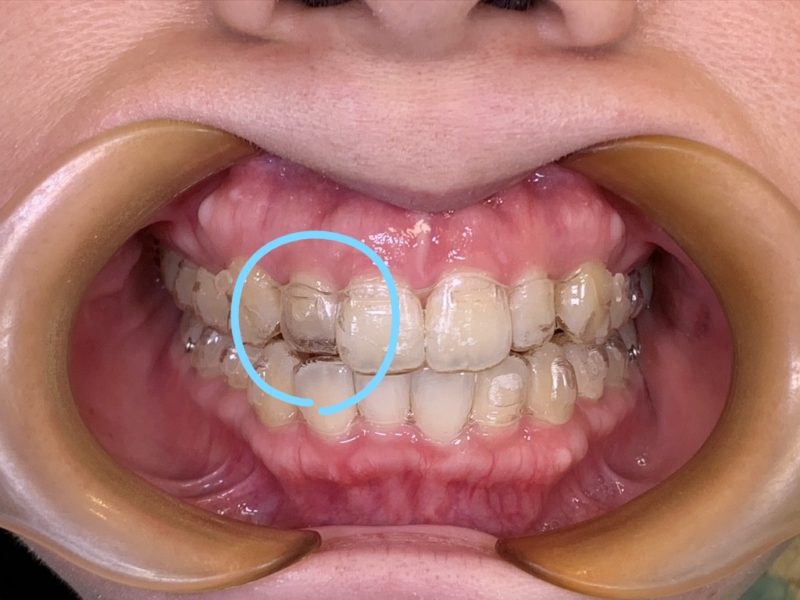

最近では様々なマウスピースメーカーが出ています。中にはイメージ通りに歯が動かないものもあります。矯正治療は一定の費用と期間がかかります。結局「理想の歯並びにならなかった」となった場合、患者さんの損失は大きなものとなります。当院では世界のドクターから評価されている世界シェアNo.1の「インビザライン」を利用していますのでご安心ください。愛知・名古屋。

患者様の歯列矯正に対してのニーズは様々です。 安いマウスピース型矯正装置(インビザライン)を利用することをベースとして、可能な限りの非抜歯矯正、 フェイスラインを整える矯正、後戻りしてしまった歯の再矯正、痛みが少ない矯正、ブライダルプランなどをご選択いただけます。 愛知県海部郡蟹江町本町にある名古屋西矯正歯科クリニック。近鉄名古屋線「蟹江駅」/JR関西本線「蟹江駅」近くの歯列矯正歯科です。 土曜・日曜も診療。駐車場完備。名古屋市からも多くの患者様が来院されます。

美しく健康的な歯並びはあなたの第一印象を変え、あなたを魅力的に映しだします。歯並びや口元はメイクではごまかせません。歯並びは、口元だけでなく顔全体の印象も大きく変えてしまう大事なパーツです。歯列矯正は見た目を良くするだけではありません。お口の中の健康増進や予防、歯の長期安定にも大切です。歯は美味しく食事をするために重要な器官でもあり、また同時に人とコミュニケーションをとるためにもとても大事なツールです。キレイな歯並びで心身共に美しく健康になっていただきたいと願っています。当院では「ゼロベース×インビザライン矯正」を主として歯列矯正を行っています。安い、治療期間が短く(短期治療)、目立たない、痛みが少ない、後戻りしにくいことが特徴です。また、患者様のニーズに合わせた、可能な限りの非抜歯矯正、フェイスラインを整える矯正、後戻りしてしまった歯の再矯正、痛みが少ない矯正、ブライダルプランなどをご選択いただけます。愛知県海部郡蟹江町本町にある名古屋西矯正歯科クリニック。近鉄名古屋線「蟹江駅」/JR関西本線「蟹江駅」近くの歯列矯正歯科です。土曜・日曜も診療。駐車場完備。名古屋市からも多くの患者様が来院されます。